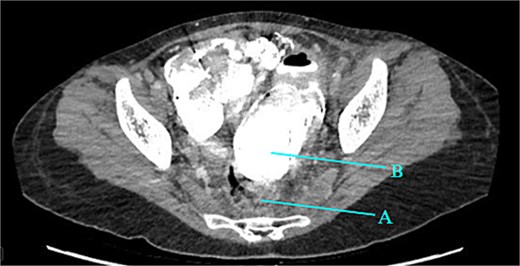

Contrast-enhanced CT of the abdomen and pelvis revealed extensive barium extravasation outlining the peritoneal cavity, accompanied by pneumoperitoneum (Fig. 3). Two barium-outlined, walled-off intra-abdominal collections were identified: one located anterior to the lower pole of the left kidney and the other in the pelvis, anterior to the rectum (Figs 4 and 5). Due to significant barium-related imaging artifacts, the precise site of bowel perforation was not identified. A diagnosis of peritonitis secondary to barium spillage was established, with associated intra-abdominal collections.

Rectum (A) large barium containing pelvic collection anterior to the rectum, the drain was placed in this collection (B).